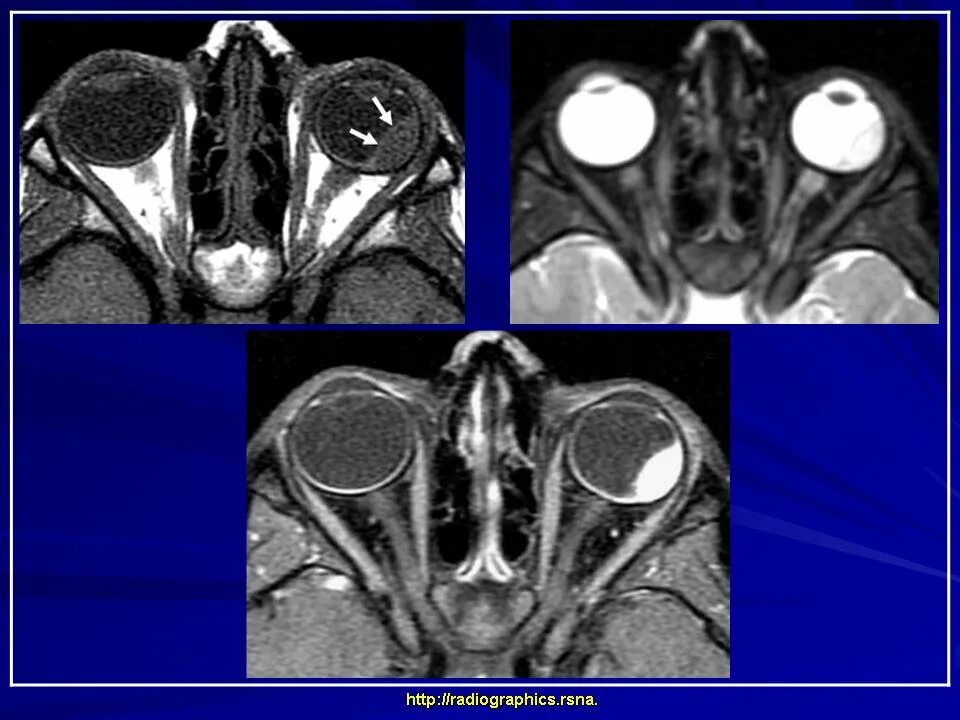

Данные кт